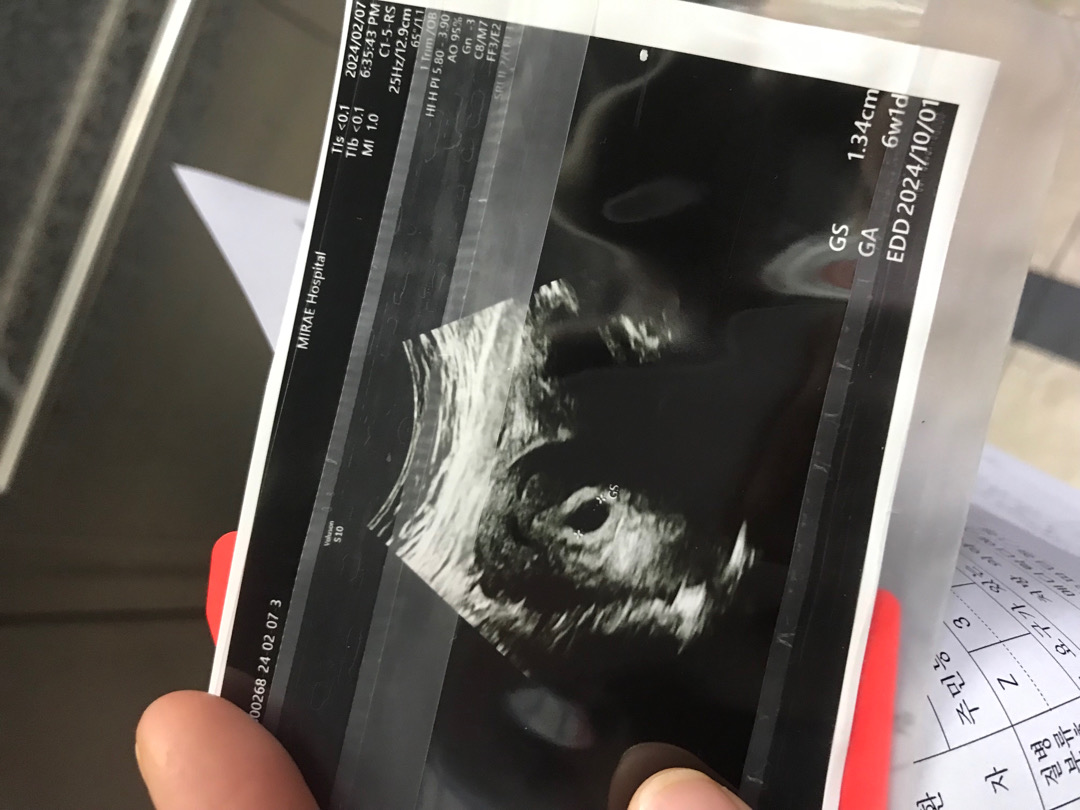

저만 난황 안보이나요ㅠㅠㅠㅠ 애가타네요ㅜㅜ

오늘 초음파 찍고 온 사진인데 다음주에 심장 소리 들으러 오라고했거든요ㅠㅠ 저번주 초음파에 0.7cm였는데 많이 크긴했는데 난황이 눈에 안보여서 불안불안해서 잠도 안오네용 ㅠㅠ